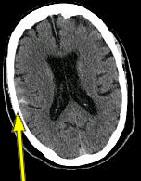

CLINICAL HISTORY: This is a 70-year-old male who presented with headaches and dizziness to the office of Dr. Pamela DeSilva* after a fall. He was referred to AIC for a head CT.

IMAGING FINDINGS: The CT was performed on AIC’s new 16-slice helical multi-slice CT (MSCT). Both routine single-slice and thin-section helical scans were obtained and 3D/Multiplanar images were performed on the Advanced 3D workstation. Fig. 1 shows an image at the level of the lateral ventricles with possible high density within the sulci on the right (arrow). To confirm this finding, an MRI with contrast was then obtained on AIC’s 1.5-Tesla high-field, short-bore Siemens MRI. Fig. 2a-b are T2-weighted images at the same level showing NO definite abnormality. T1-weighted images (not shown) were also negative. The post-contrast images (not shown) showed NO abnormal enhancement in this region, either. Diffusion-weighted images were also negative. However, Fig. 3a-b, which are FLAIR images, demonstrate clear hyperintensity within multiple sulci involving the right temporo-parietal area (arrows).

DIAGNOSIS: The FLAIR images are compatible with Subarachnoid disease. The Differential Diagnosis includes: (1) Subarachnoid Hemorrhage (SAH); (2) Meningitis; (3) Infarct; (4) Flow Artifact. Lack of enhancement is against meningitis. Acute infarct was ruled out on the basis of negative Diffusion MRI and lack of cytotoxic edema on the FLAIR images. Focal abnormality is against flow artifact (which is more diffuse and usually in the posterior fossa on FLAIR images). The clinical history of trauma and the high-density on CT and hyperintensity on FLAIR images within the sulci are diagnostic of Acute Post-traumatic Subarachnoid Hemorrhage (SAH).